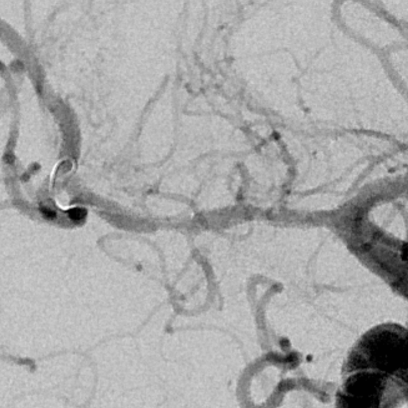

乍一看血管似乎还可以

重建的形态

放大后仔细观看,近端有局限性血管变细,并见双腔征

另外时相远端也隐约局限性变细

观察,血管形态还可以,血流顺流

继续观察